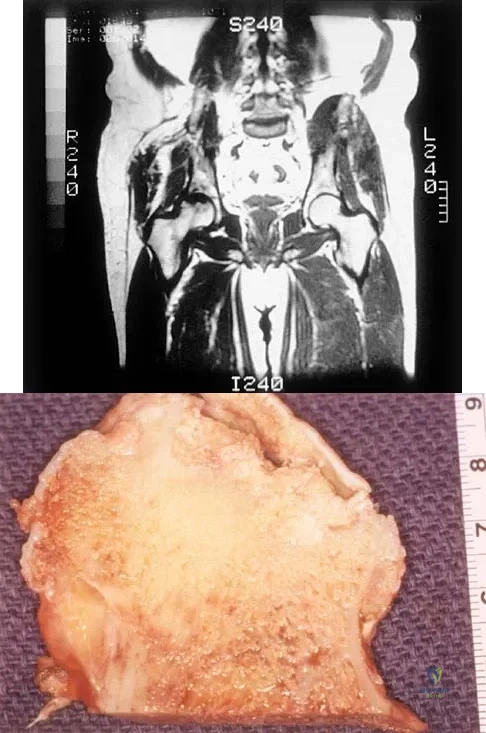

A 51-year-old male truck driver has had progressive left hip pain for more than 2 years, and he reports that the pain has become severe in the past 9 months. He is now unable to work because of the pain. Examination reveals that range of motion of the hip is limited to 95 degrees of flexion, 0 degrees of internal rotation, and 20 degrees of external rotation. The plain radiograph, MRI scan, and intraoperative gross photographs are shown in Figures 9a through 9d. Management should consist of

Explanation:

The diagnosis is synovial chondromatosis. While the plain radiograph fails to show any calcifications, the MRI scan shows an intra-articular mass that involves the capsule. Grossly multiple granular cartilage nodules are seen. Management should consist of removing all loose bodies along with the synovial membrane.